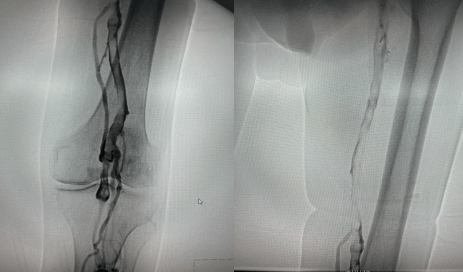

術中造影左下肢股靜脈、腘靜脈大量血栓形成

為預防肺栓塞及血栓后遺癥,緩解老人癥狀,最大程度減少瓣膜破壞;延安大學咸陽醫院周圍血管介入團隊急診為患者進行下腔靜脈濾器置入、經導管血栓清除術、接觸性導管溶栓治療。

術中導管抽吸血栓、留置溶栓導管